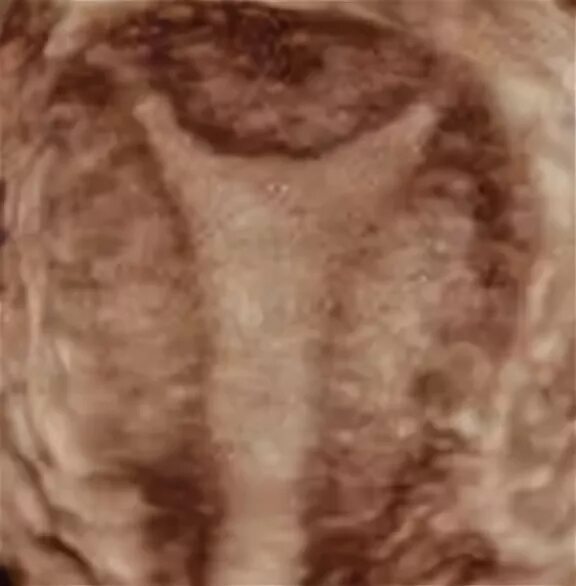

Что такое две матки у женщины